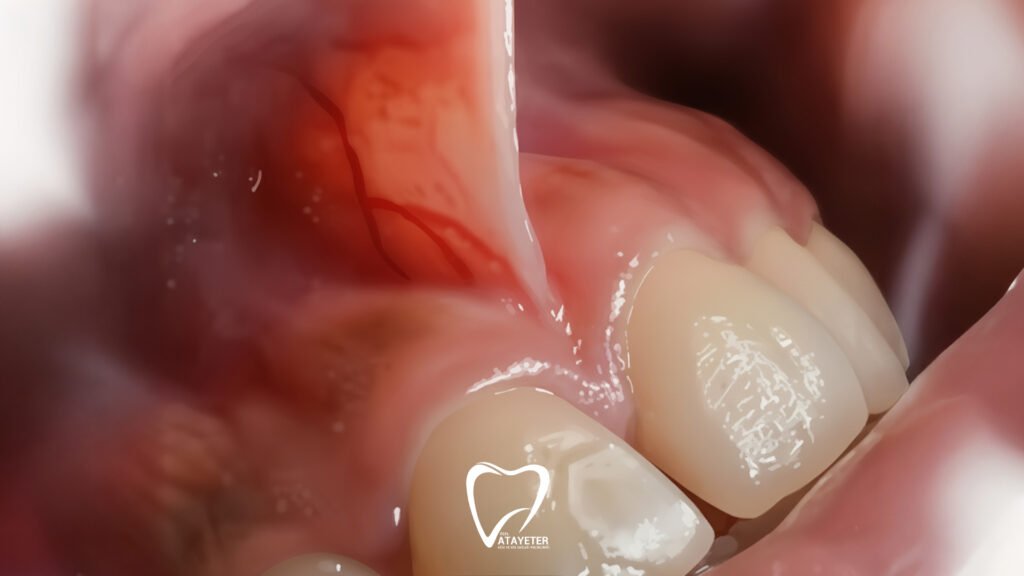

En sık karşılaşılan nedenlerin başında dil bağı (ankiloglossi) gelir. Dil altındaki frenulumun kısa olması, dilin yeterince hareket edememesine ve buna bağlı olarak konuşma bozukluklarına yol açabilir. Özellikle bazı harflerin telaffuzunda zorlanma, çocuklarda ve yetişkinlerde sık görülen bir durumdur. Bebeklerde ise bu sorun emme ve beslenme güçlüğü şeklinde kendini gösterebilir.